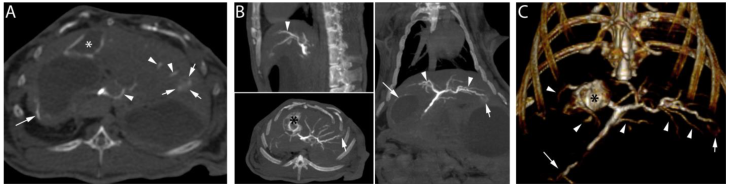

Following the embolization procedure with RO Beads suspended in soluble contrast medium and euthanasia, high dose CBCT demonstrated contrast retention in the tumor (Figure 7, short arrows) and opacification of hepatic arteries (Figure 7, arrow heads). Furthermore, non-target embolization of extrahepatic arteries (Figure 7, long arrow) was clearly observed. In general, RO Beads in soluble contrast medium had improved imaging appearance in target and non-target blood vessels compared to LC Bead delivered in soluble contrast medium. RO Beads conspicuity was durable in vivo, lasting to at least 7 days (data not shown).

Figure 7

High dose CBCT performed post-euthanasia after the delivery of 1.1 cc of RO Beads suspension (0.055 cc RO Beads sedimented volume) delivered in iodinated soluble contrast medium. A) Axial image: contrast retention in the tumor is observed (short arrows). Linear attenuation in the wall of the gallbladder (asterisk) and hepatic arteries (arrowheads) are evidenced. Non-target delivery is shown in a gastric artery in the wall of the stomach (long arrow). B) Multi-planar reconstruction demonstrated contrast retention in the tumor located in the left hepatic lobe (short arrows). Linear attenuation consistent with a tumor feeding and normal hepatic arteries is also shown (arrowheads). Contrast retention is observed in the wall of the gallbladder (black asterisk). Non-target delivery is shown in gastric arteries and the wall of the stomach (long arrow). C) 3D volume rendering image in coronal view demonstrating the hepatic arteries (arrowheads), non-target delivery (long arrow), the tumor located in the left hepatic lobe (short arrow) and hyperattenuation of the wall of the gallbladder (black asterisk).